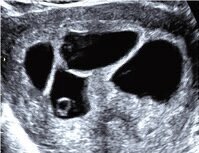

Vierlingsschwangerschaft (4 Fruchthöhlen – tetrachorial)